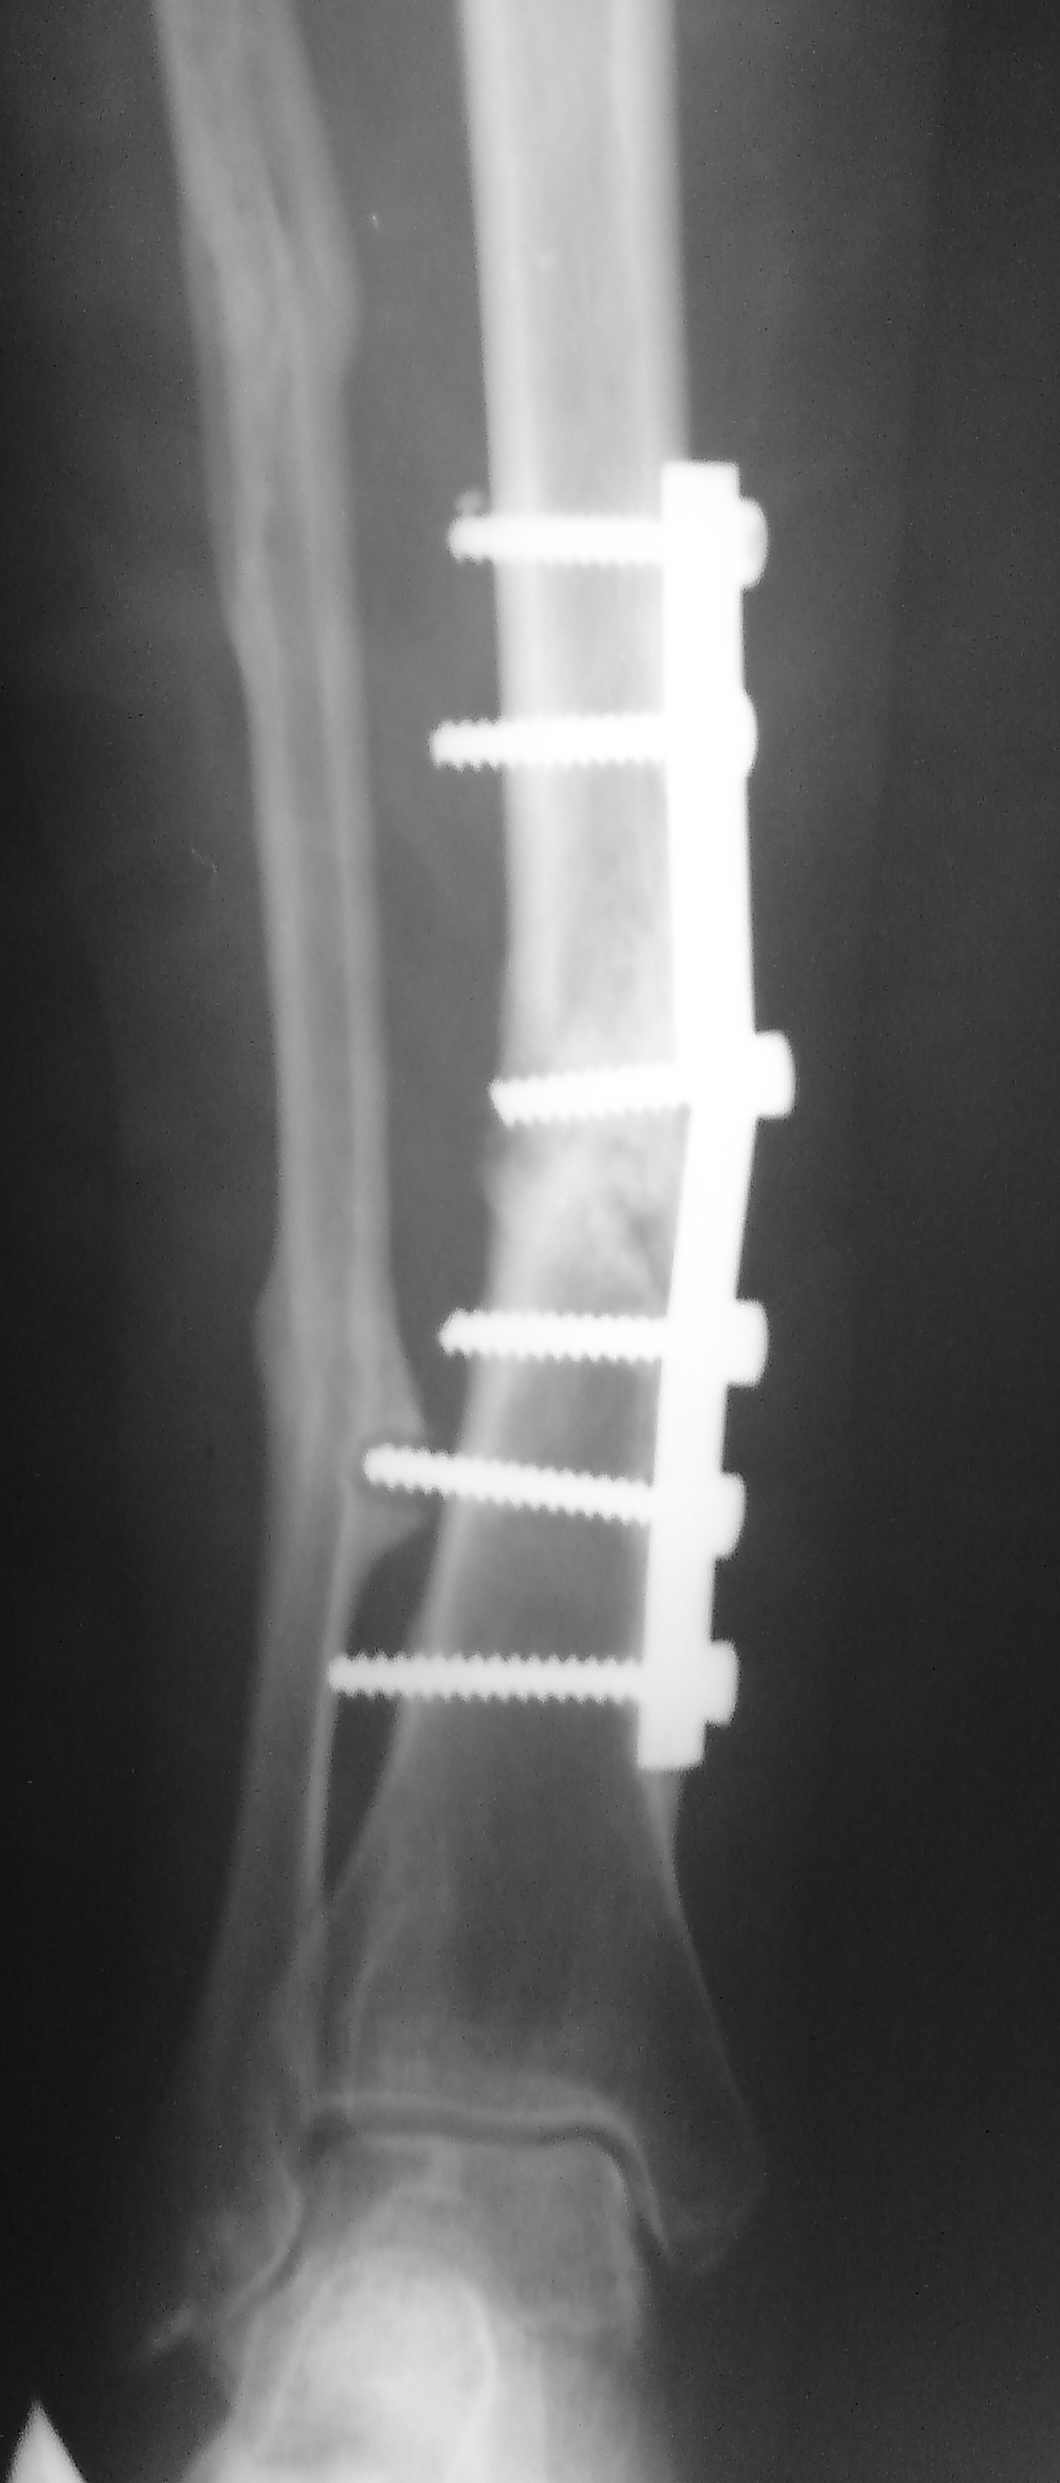

Ложный сустав н/3 б/берцовой кости |

Здравствуйте уважаемые коллеги.В нашу клинику обратилась б-ая 48 лет, Здравствуйте уважаемые коллеги.В нашу клинику обратилась б-ая 48 лет,перелом обеих костей голени в 2006 ,ВЧОС по Илизарову;операция по поводу ложного сустава 2008.Хотелось бы узнать Ваше мнение по тактике дальнейшего лечения

Мне кажется нужно делать то, чем лучше владеете. Или ставить более длинную пластину, желательно блокируемую, с остеотомией малоберцовой кости, костной аутопластикой и центральные винты подальше от ложного сустава. Или интрамедуллярный блокируемый остеосинтез. Тоже с остеотомией малоберцовой. А точно ложный сустав? По одной проекции и не скажешь. Иногда после перелома пластины срастается.

Доброго времени суток! Мне кажется можно попробовать БИОС, с применением в область перелома пластических материалов если не будет укорочения конечности после открытия каналов. Или же если имеется укорочение наверное даже лучше пластика дефекта и АВФ по Илизарову.

Мы бы малоинвазивно убрали пластину (взяв посев на всякий случай), чрескожно пересекли малоберцовую. И можно далее постепенно аппаратом восстановить ось и заштифтовать. И можно одномоментно, сделав чрескожную остеотомию большеберцовой ниже псевдартроза.

В принципе, можно и все остальные виды остеосинтеза тут использовать.

Поэтому лучше конкретизировать, какие именно моменты побуждают представить этот случай, в чем тут сомнения или затруднения.